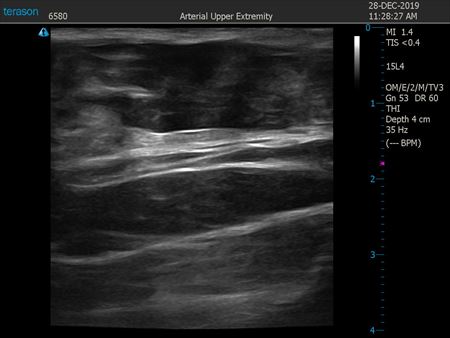

いつものように3Dタッチビュー(超音波)で

皮下脂肪層を評価してみましょう。

上腹部